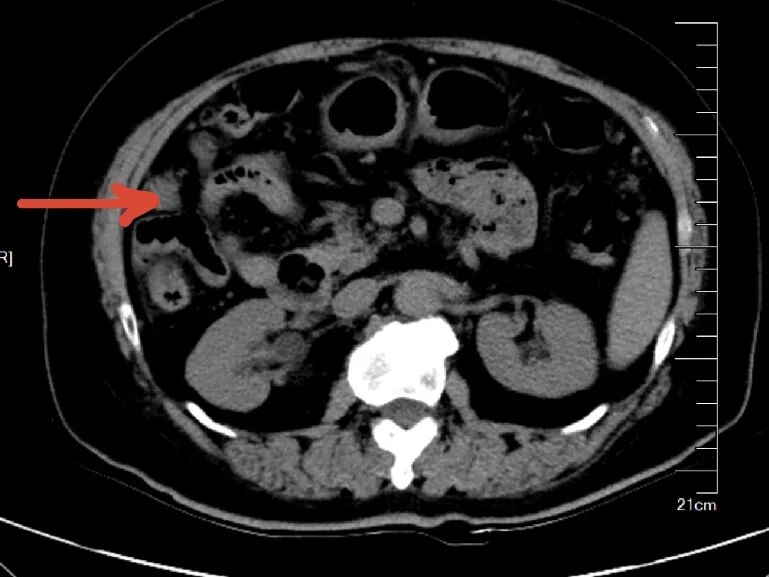

65岁的陈女士,因反复口干、多尿多饮、伴疲劳乏力,偶有胸闷,监测空腹指尖血糖超过11mmol/L,来我院内分泌科住院治疗,入院后完善相关检查,其中在子宫双附件彩超筛查中发现子宫上方见一类圆形低回声团,大小约37x32x37mm,边界不清,内部回声不均匀,这意味着不排除肿瘤可能。在积极控制血糖的同时,进一步完善了盆腔MR增强等针对性检查,结果提示:双侧附件区、

子宫直肠陷凹

及子宫周围多发结节状、团块状异常信号影,考虑附件区恶性肿瘤, 伴子宫直肠陷凹及子宫多发转移。内分泌科主任颜文盛考虑到该患者病情复杂,立即申请妇科会诊。经过妇科团队会诊,近期可能需要专科手术干预治疗,他与家属充分沟通后,家属果断选择转入广州市花都区人民医院妇科。